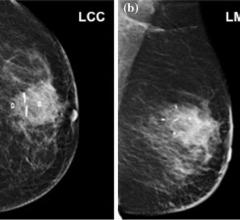

In 2017, invasive breast cancer will be diagnosed in about 252,710 women and 2,470 men in the U.S. and remains the second leading cause of death in women, according to the American Cancer Society. Advances in technology continue to become available to aid in the fight against breast cancer which can improve the chances of beating the disease. David Weintritt, M.D., founder of the National Breast Center and National Breast Center Foundation, recently identified the top three technologies impacting the future of breast cancer treatment to improve outcomes for women diagnosed with the disease.

The trend in breast cancer treatment these days is all about precision, with the twin goals of controlling the cancer better and reducing side effects. Great advances have been made in radiation delivery methods that make it possible to more precisely target the tumor bed, plus a small margin around it where the cancer would be most likely to recur. By tightly focusing on these areas alone, radiation oncologists can minimize exposure to critical healthy tissue and structures such as the heart and lungs. Less damage to healthy tissue also means better cosmetic outcomes.